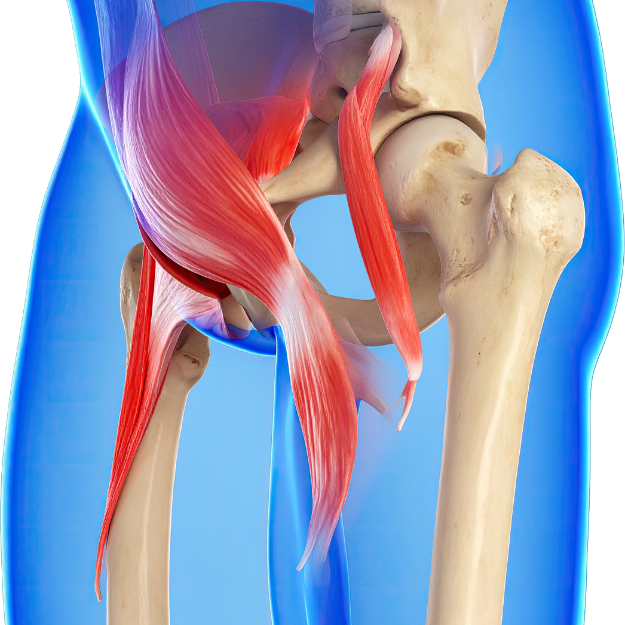

How Pelvic Floor Muscles Work

What Are Pelvic Floor Muscles?

Pelvic floor muscles are a group of muscles located at the bottom of the pelvis. They form a strong supportive structure that holds important organs in place, such as:

These muscles act like a hammock that supports all pelvic organs. When these muscles become weak, many health issues can develop, and proper pelvic floor dysfunction treatment becomes necessary.

Main Functions of Pelvic Floor Muscles

1. Support of Internal Organs

The pelvic floor muscles keep the bladder, uterus, and bowel in their correct position. If the muscles are weak, problems like prolapse can occur.

3. Core Stability

Pelvic floor muscles work together with abdominal and back muscles to provide stability to the spine. This is why physiotherapy for pelvic floor is also important for improving posture and back pain.

How Do Pelvic Floor Muscles Work?

Pelvic floor muscles work in coordination with breathing, core muscles, and daily body movements.